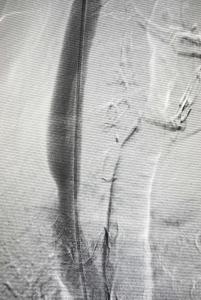

Nel nuovo studio si è quindi proceduto alla rivalutazione, utilizzando una metodologia rigorosa e in “doppio cieco”, delle flebografie dei pazienti arruolati nel Brave Dreams. Una Commissione esterna ha visionato indipendentemente i filmati delle procedure e applicando il “Giaquinta Grading System” è stata in grado di distinguere due categorie di pazienti: ‘favorevoli’ e ‘sfavorevoli’.